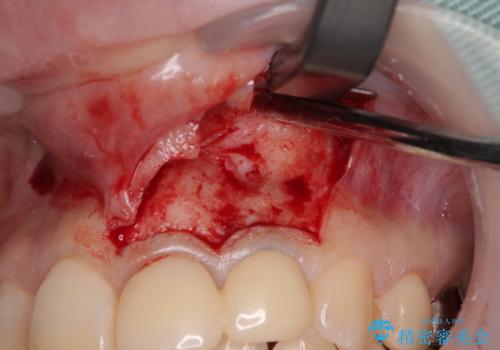

以前歯根端切除術を受けているものの、現在の主流とは異なる術式で行われているため、再度歯根端切除術を行うこととしました。

痛みが改善したことを確認した上で、オールセラミッククラウンにて補綴治療を行うこととしました。